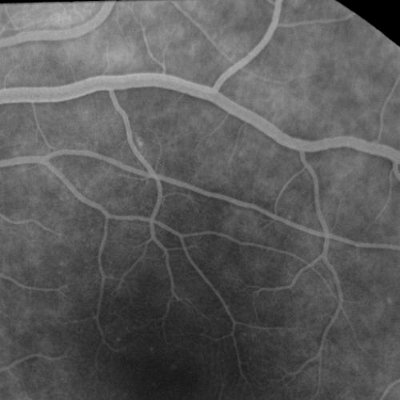

Colour photographs and green photographs are taken first of the retina usually of a 'straight ahead' view which will show the area of sharpest vision (macula). After that a butterfly needle or ventflon (plastic tube) is placed in an arm or hand vein and the dye is injected rapidly over 5 seconds. After around 14 seconds the dye starts to be seen circulating in the blood vessels of the retina and a rapid sequence of flash photos is taken for the first minute or so. After that photos may be taken of the peripheral parts of the retina usually four quadrants; and of the other eye. The last photographs are taken at 5 minutes from the initial dye injection.Shown below are two examples of flourescein angiograms. The first one shows a normal appearance. The dye passes through the blood vessels with no "blockages" and no leakage. The vessels look nice and sharp. Take a look at the second one and you will see the dye "leaking" out of the blood vessels, which look rather fuzzy. this angiogram comes from a patient who has active uveitis.

1. Normal angiogram